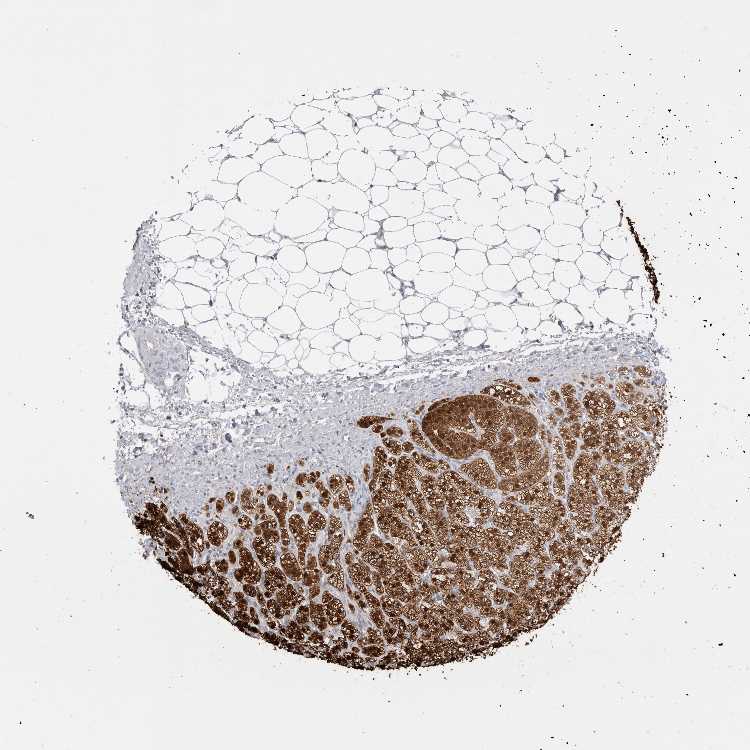

ADRENAL GLAND - Antibody stainingi

Antibody staining in the annotated cell types in the current human tissue is reported as not detected, low, medium, or high, based on conventional immunohistochemistry profiling in selected tissues. This score is based on the combination of the staining intensity and fraction of stained cells.

Each image is clickable and will lead to virtual microscopy that enables deeper exploration of all samples and also displays staining intensity scores, fraction scores and subcellular localization as well as patient and tissue information for each sample.

Antibody CAB022745

Glandular cells High